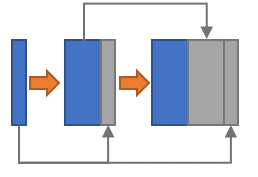

Three popular CNN blocks are utilized to modify the network structure. The dense block [8] is inserted in each level of the encoder path. The side-output layer [3] is employed to provide deep supervision in the decoder path. And the residual block [9] is integrated into the encoder, the bottleneck as well as the decoder. The block structures are illustrated in Fig. 1 (b-d).